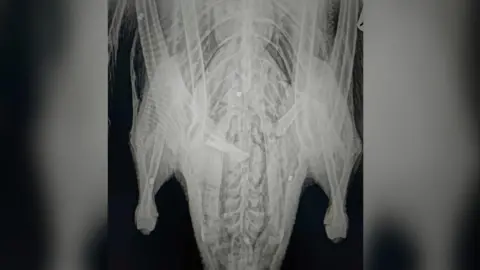

An X-ray showed the swan had been shot with eight pellets, which were found in its body, leg and head.